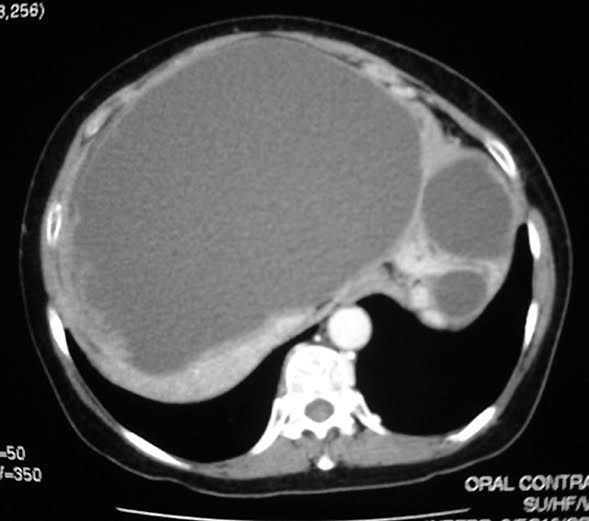

Hydatid disease is a parasitic infestation of humans caused by Echinococcus granulosus. Dogs and some wild carnivores like foxes are definitive hosts, harbouring worms in their intestine. Eggs are passed in the faeces and eaten by the intermediate hosts, and larvae encyst in the liver, lungs, and other organs.